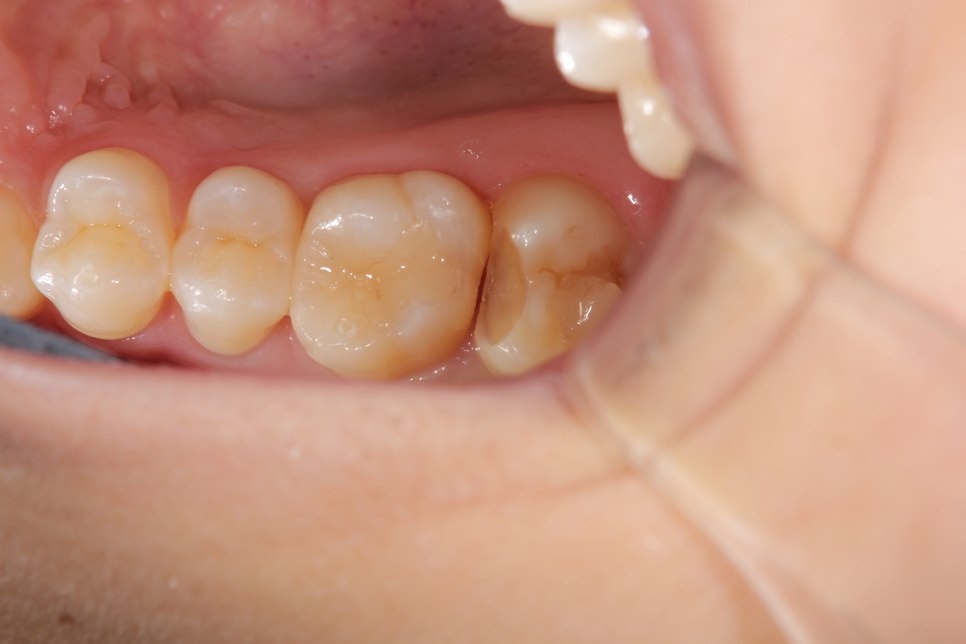

奥歯がしみるとの事でした。一見分かりませんが拡大鏡で確認して行くと虫歯が見つかりました。

虫歯を取った状態です。虫歯のみを取っています。

ここにマトリックスという金属製の薄い器具を入れて行き歯の形をなるべく再現できる様にします。

治療後の状態です。通常の型とりをする治療だと今回の数倍歯を削る事になります。歯は削れば削る程、脆くなりますので治療する事で歯の寿命を縮める事にもなり兼ねません。今回、最小限度のダメージで回復できました。歯も長持ちする事でしょう。

ダイレクトボンディング

費用6万円

リスクとして欠ける可能性がある(修復可能)。